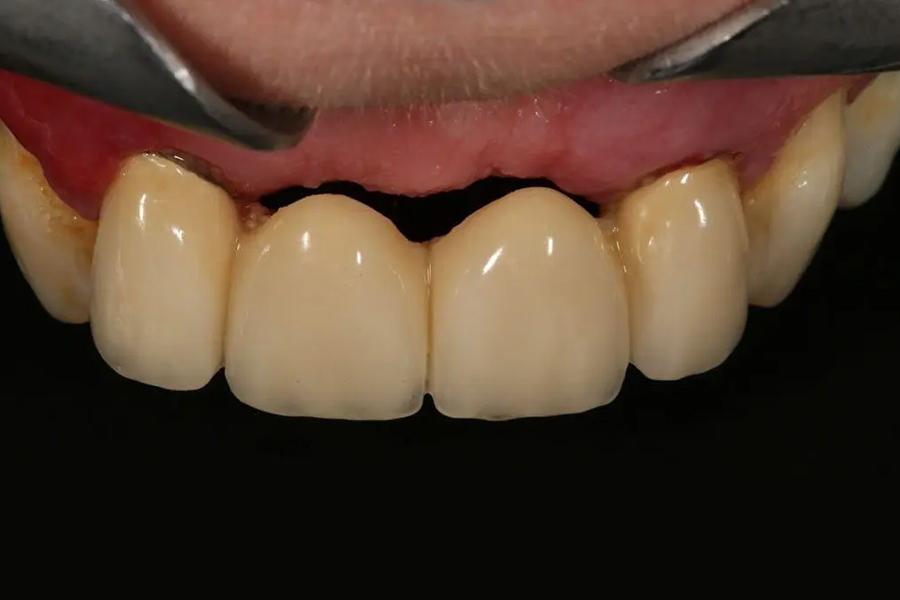

Cầu răng sứ

Phương pháp cầu răng sứ là kỹ thuật phục hình răng cố định bằng cách mài hai răng thật bên cạnh khoảng trống mất răng để làm trụ, sau đó bắc cầu các mão răng sứ liền kề lên trên.

Cầu răng sứ có tính thẩm mỹ cao, ăn nhai ổn định. Tuy nhiên, nhược điểm là bắt buộc phải mài bớt hai răng thật khỏe mạnh ở hai bên để làm trụ, điều này tiềm ẩn nguy cơ ê buốt, sâu răng trụ về lâu dài. Bên cạnh đó, cầu răng vẫn không thể ngăn tiêu xương hàm tại vị trí mất răng vì không có chân răng trực tiếp kích thích xương.

Cầu răng sứ gây ra tình trạng tiêu xương hàm sau thời gian sử dụng.